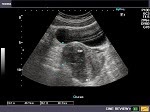

When her Gynecologist, told her to go for ultrasound, on 5th March, 2013 - it found that there is sub serosal fibroid attached to posterior wall with dimensions of 3.4 and 5 cms.

On 11 April’13 she came saying that her menses are become regular, her stomach fullness also reduced. i told her to repeat the ultra sound after 1 month. In May she came back with ultrasound pelvis, saying that, fibroid size reduced to 1.5 and 2.5 cms. She is still on treatment and there are no significant problems in her health conditions.